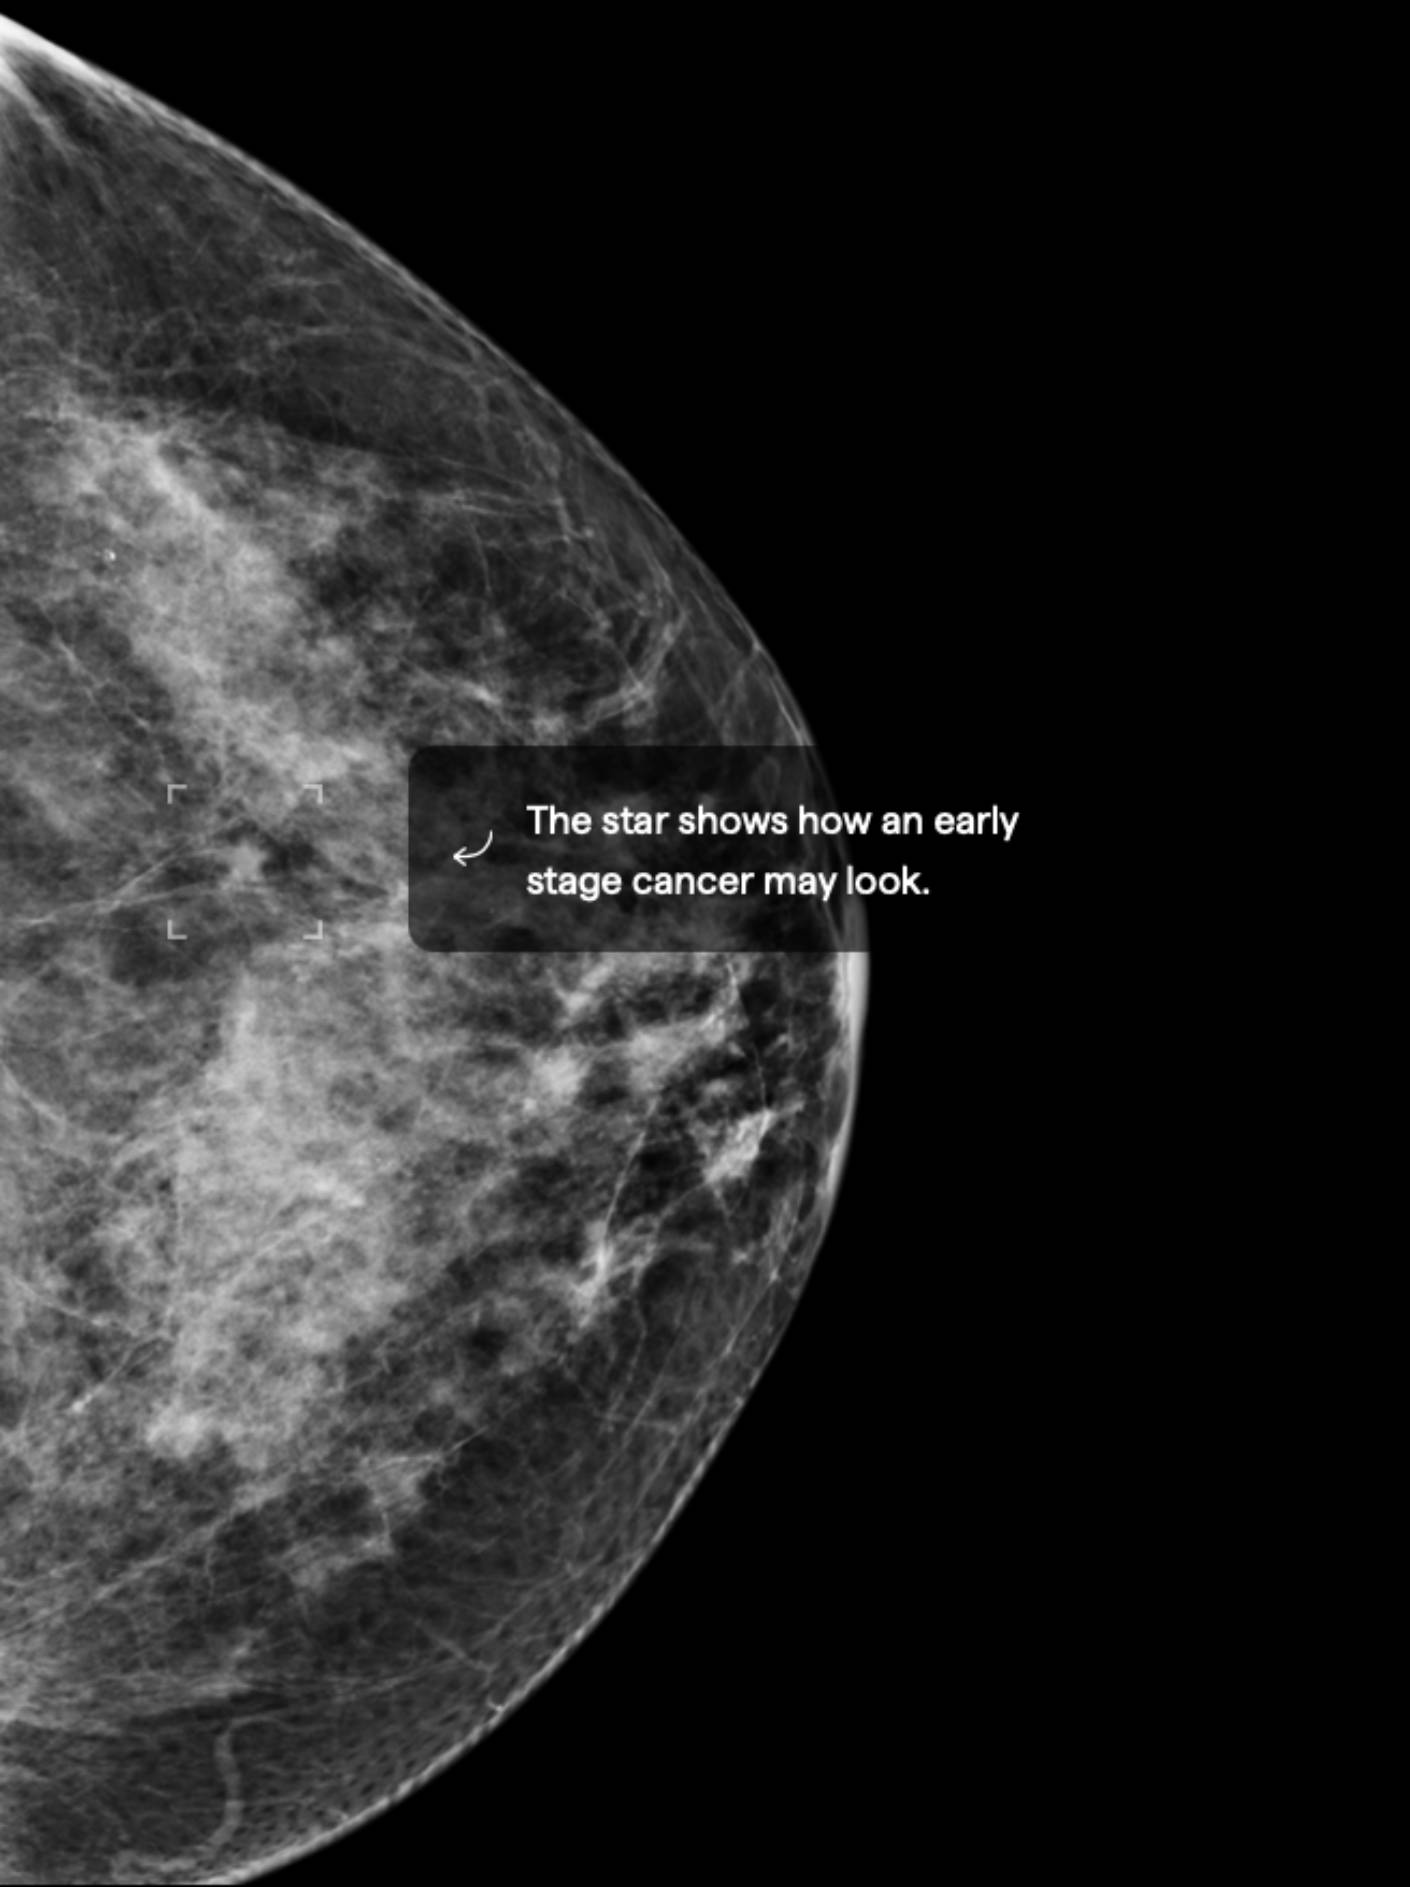

15.5% Mammographic Density

About 10% of female breasts fit category “D”. They are referred to as “extremely dense breasts”.1

Women with high breast density may have a greater risk of developing breast cancer. High breast density also makes it harder to detect breast cancer.3 Consider asking your doctor about adding ultrasound and/or MRI imaging to your screening schedule. Also consider asking about a risk assessment to help both of you better understand your lifetime risk for breast cancer.